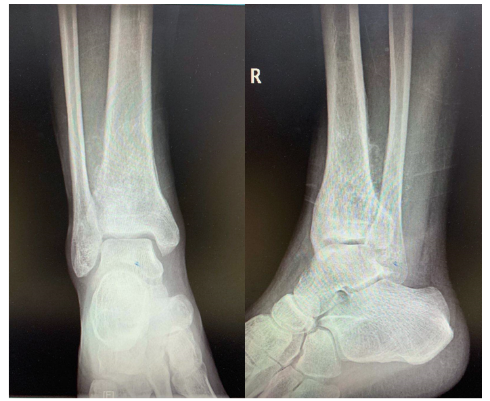

术前X线照片

几经诊治后,患者最终来到了珠江医院,关节骨科主任医师林荔军根据自己多年的诊治经验判断,考虑患者胫骨远端肿块可能是骨恶性肿瘤,在完善各项术前检查后,林荔军主任和他的团队在C臂引导下对肿块进行了取样活检,术后病理报告为:“成软骨型骨肉瘤(低中级别)”,结果也证实了他的猜想。骨肉瘤是骨肿瘤里面恶性程度极高的一种,骨肉瘤病人早期容易发生肺部转移,死亡率极高。对于骨肉瘤,尽早的诊断和彻底的手术切除就变得十分关键。而发生在胫骨远端的骨肉瘤,更为罕见。如何彻底地切除肿瘤,达到根治的目的同时,还要考虑保留患者功能的踝关节功能及行走功能需求,这是摆在医生及患者面前的极大挑战。